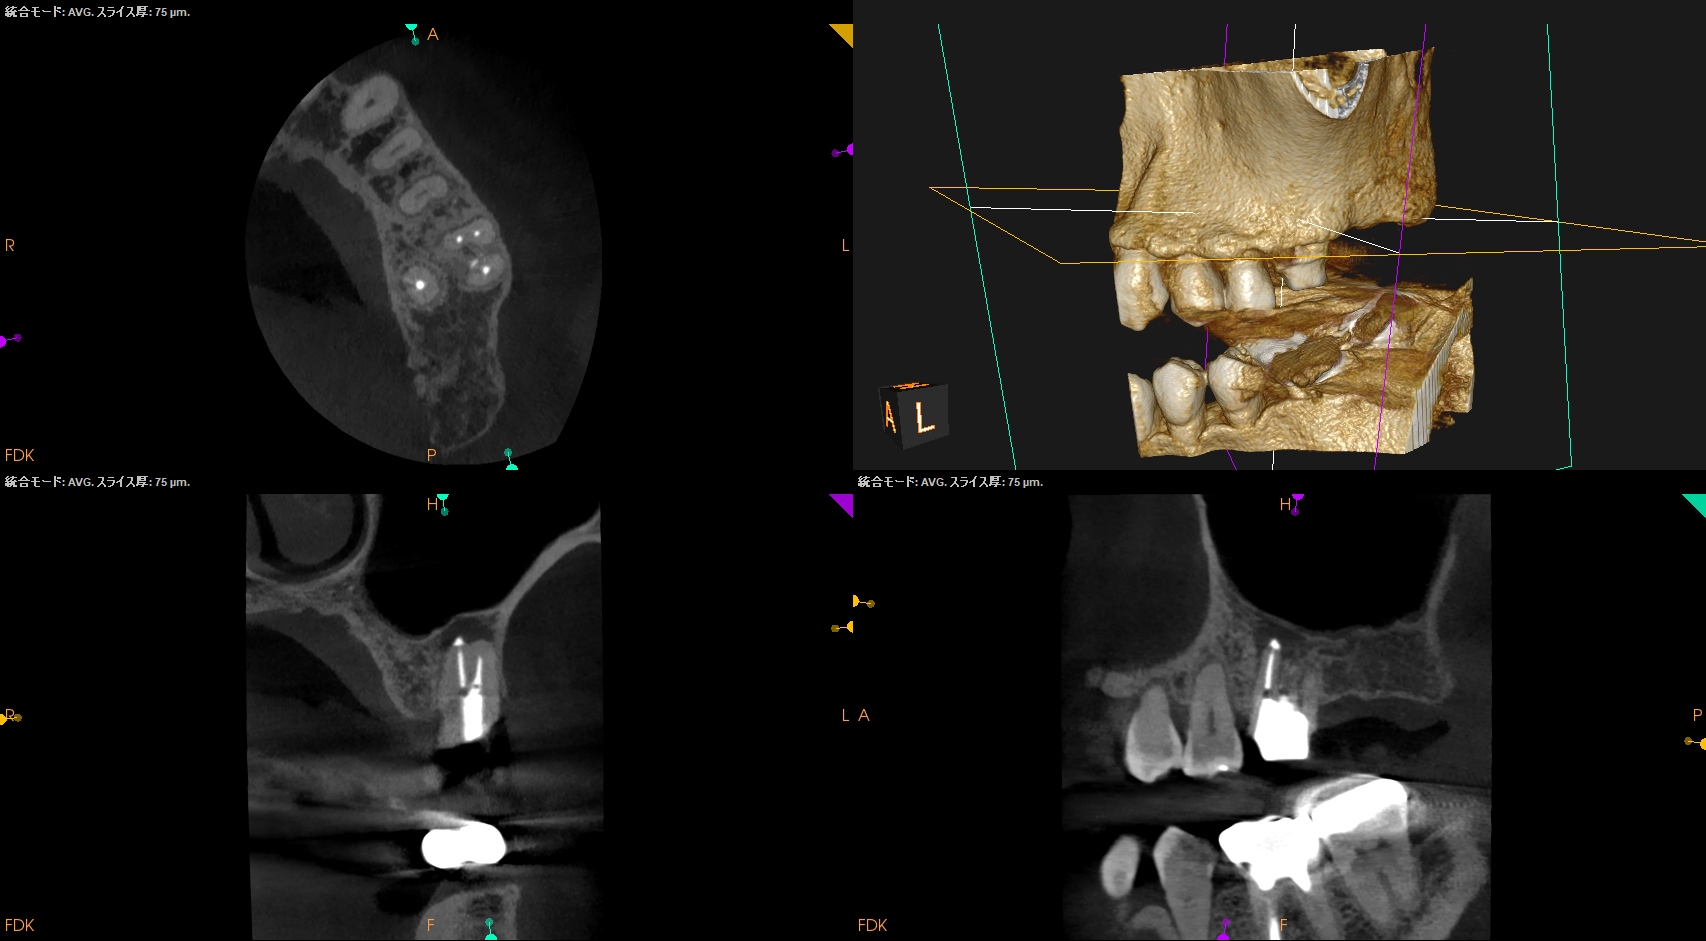

この際の切断面が上記のCBCTの絵の咬合面観に相似であるので問題がない、ということもわかるだろう。

CBCTを参考にCEJよりDBのApexを測定し該当部位をOsteotomyし、Root resectionし、メチレンブルーで染色した。

この際の断面が上記のCBCTの絵に掃除であれば問題ないが、切り残し(アゴ)が残存したので切断し直している。

術後にPA, CBCTを撮影した。

MB

DB

問題はないだろう。